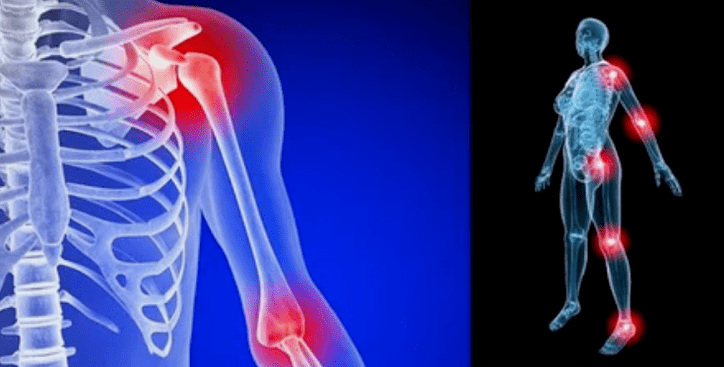

The manifestations of the disease differ little, depending on the location, more often the signs are reflected in the knees, shoulder joints and hip due to high load.

Mainly complaints come down to:

- pain.They have low severity in the early stage, with intensified sensation state.Initially, the joints hurt only after waking up, after a light and hot, the sensations disappear.Over time, the pains appear at night, they disturb a lot during and after the prolonged walk, running, etc.In the last stage, pain syndrome chases a person all the time;